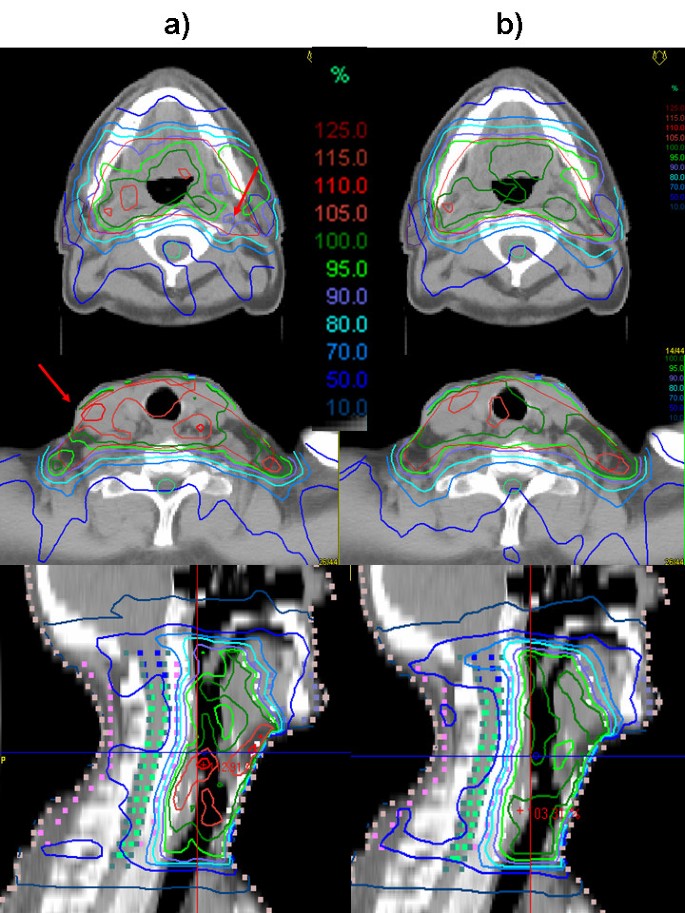

Figure 1 shows a comparison of the isodoses generated with IM and DSS for two representative transversal slices and the central sagittal plane of one of the patients. Figure 2 shows the corresponding DVH. Mean values, standard deviations and p-values of selected DVH points of all patients are given in table 3. The evaluation of the treatment plan quality by means of DVH showed a significant difference for the PTV coverage and homogeneity (p < 0.05). Target coverage given by the mean value of V95 was significantly lower for IM plans (81.0% ± 8.3%) than for the DSS plans (91.9% ± 3.3%) (p = 0.002). V107 was larger for IM (6.7% ± 2.5%) than for DSS (0.9% ± 0.9%), with a p-value p < 0.0005. The mean value for the homogeneity, given by the relative dose difference H = (D5 - D95)/Daverage of the DVH of the PTV, was higher for the IM plan (18.9% ± 5.4%) than for the DSS (10.8% ± 1.7%, p < 0.0005), which means the DVH was steeper and a significantly more homogeneous dose distribution inside the target could be achieved with DSS. Daverage was in the same range for both techniques with 55.7 Gy ± 1.0 Gy (IM) and 56.0 Gy ± 0.2 Gy (DSS).

Isodoses of the plans optimized with a) IM and b) DSS for one of the patients in two representative transversal slices and the central sagittal plane. The better target coverage is visible particularly in the region around the right parotis. The red arrows point out regions of underdosage in the plan optimized with IM.

The dose to the parotids was lower for the IM optimized plans than for the DSS plans with a mean dose of 19.0 Gy ± 2.4 Gy (IM) and 22.0 Gy ± 1.6 Gy (DSS) for the left parotid (p = 0.007) and 20.4 Gy ± 1.8 Gy (IM) and 21.9 Gy ± 0.9 Gy (DSS) for the right parotid (p = 0.03). The maximum dose to the spinal cord was comparable in both cases with 31.1 Gy ± 2.9 (IM) and 30.5 Gy ± 3.2 Gy (DSS). The maximum dose to the external contour was higher for IM (64.3 Gy ± 1.3 Gy) than for DSS (62.2 Gy ± 1.3 Gy).